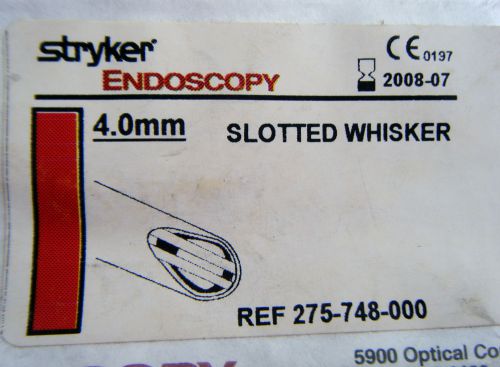

STRYKER Formula Endoscopy SLOTTED WHISKER Cutter Shaver 4.0mm 275-748-000 new